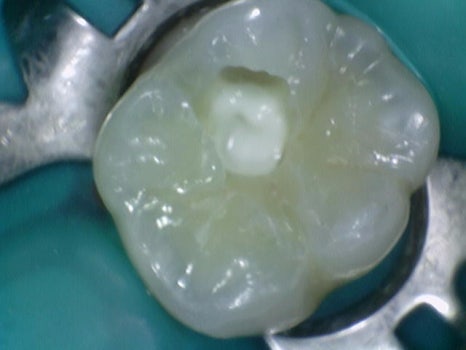

치료 후 사진입니다.

노출된 신경관 입구에 MTA 재료를 쌓아 올린 후 경화된 후

상부에 튼튼하고 심미적인 레진 치료 후 마무리를 했습니다.

신경이 살아있고 노출 범위가 넓지 않기 때문에 MTA 재료의 아주 좋은 케이스입니다.